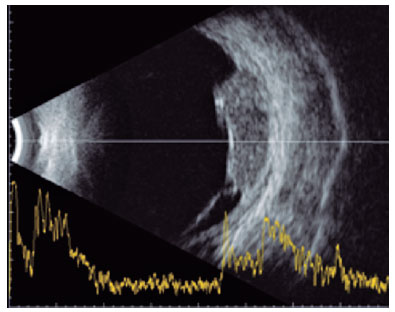

The ophthalmologic evaluation revealed a best-corrected visual acuity of 20/20 in the right eye (oculus dextrus [OD]) and counting fingers at 1.5 m in the left eye (OS). No changes were found on the biomicroscopy of the anterior segment in either eye (oculus uterque [OU]), including no anterior chamber or vitreous reaction. The intraocular pressure was 12 mmHg in OU. Fundoscopy revealed no abnormalities in the OD but revealed a large yellowish choroidal lesion in the temporal region of the posterior pole of the OS, with mild subretinal hemorrhage, associated with serous detachment of the perilesional retina (Figure 1A). US of the OS confirmed the presence of a choroidal mass temporally to the fovea, with medium and homogenous internal echogenicity, associated with serous retinal detachment (Figure 1B).